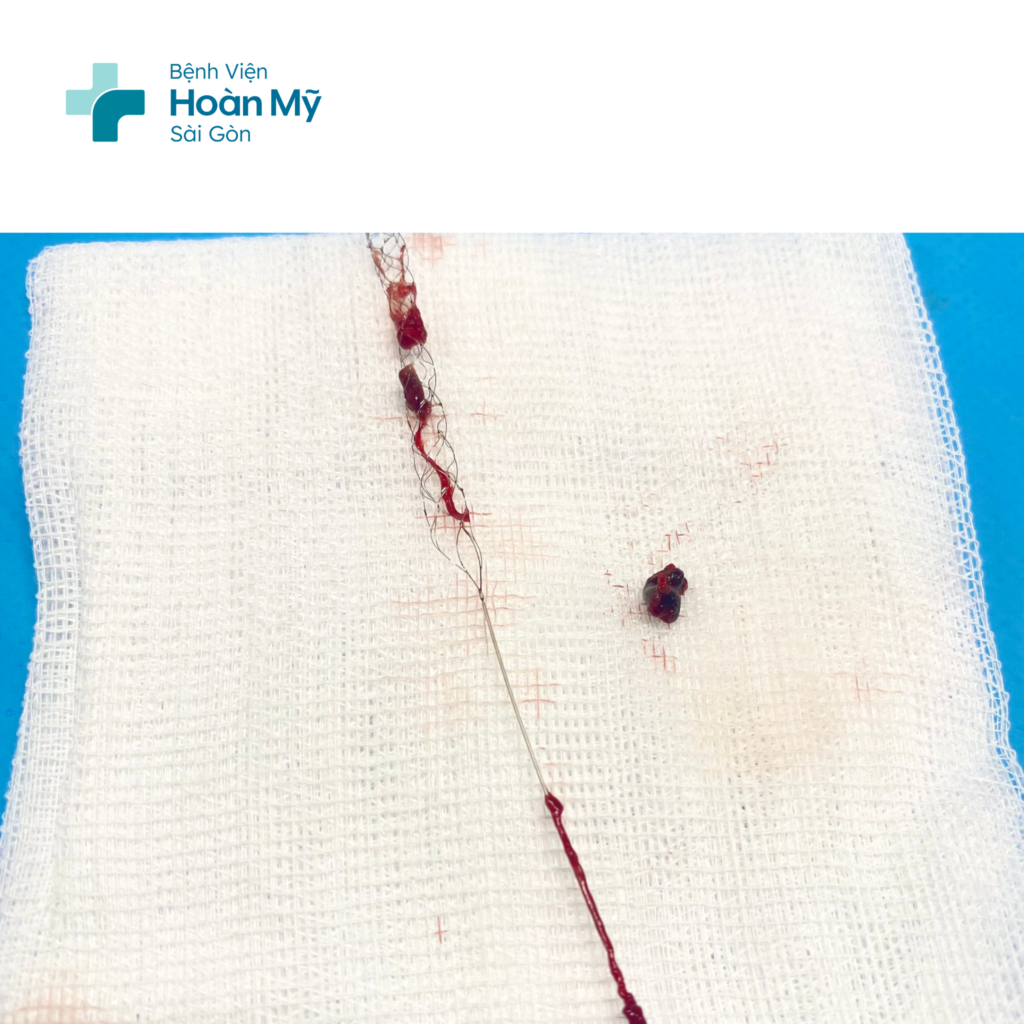

Tại đây, các bác sĩ tiến hành dùng dụng cụ chuyên biệt để đưa lên động mạch não, lấy cục máu đông đang làm tắc mạch máu của người bệnh. Khoảng 30 phút sau khi can thiệp, tình trạng người bệnh cải thiện, chân tay đã cử động được.

Hình ảnh huyết khối được lấy ra